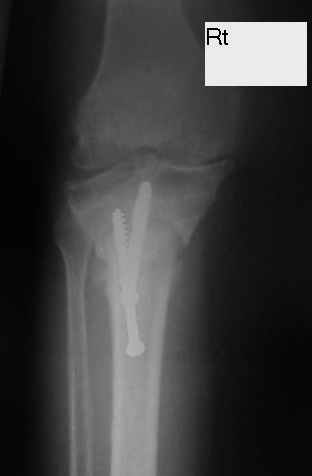

Dorogie Kollegy,Ko mne obratilas' bol'najia, ei 64 goda, ona stradaet ot dvuhstoronnego varusnogo gonoartroza, ei bila vipolnena Visokajia Ostotomjia goleny sprava 01.06.2004, zona osteotomii ne sroslas', plastina bila udalena 12.09.2004 (vidimo iz-za ee nestabilnosti), zona osteotomii tibia bila fixirovana 3-mjia shurupami. Seachas sylno bespokoyat boly v dvuh sustavah, hodit s trudom s pomoshyu Walker, a voobshe ona seachas na invalidnoi kolyaske. Podzkazite, pozhalusta, kak mozno ei pomoch' (snimky prilagayutsa)

Уважаемый Dr.Castro. Мне кажется возможной причиной несращения перелома явилось затекание синовиальной жидкости в зону остеотомии. Проксимальный фрагмент б.берцовой кости мал и "неудобен" для фиксации. Как вариант - можно предложить ЧКДО по Илизарову с временной фиксацией н.з бедра с целью усиления стабильности.Но с аппаратом придется повозиться ( поиграть фрагментами голени).Если нет возможности или желания заниматься аппаратом, придется выполнить СТАБИЛЬНЫЙ остеосинтез мыщелковой или г-образной пластиной, но обязательно с аутопластикой области несращения. Или в виде аутокрошки, или путем перемещения костного трансплантата с дистального фрагмента б.берцовой кости кверху с перекрытием области несращения.

Уважаемый Dr.Castro, я абсолютно согласен с коллегой на счет первого варианта. Использовать пластину с угловой стабильностью не советую поскольку у нас были случаи несращения в этой области при использовании Г-образных пластин после первичного остеосинтеза.В даном случае нужна постоянная и мощная компресия которую можно достичь только методом Илизарова.

U bol'nogo non-union osteotomii tibii. V vozraste 64 let, sdelal bi sleduiezhee:

1. I predpochel bi ego: Total Knee Arthroplasty. Nuzhen budet Revision ( Long stem) tibial Component.

2. Ne sovetuiu delat' geroicheskix postumkov v otnoshenii Non union. Tut est' mnogo problem, ved' esteotomia provedena ne pravili'no s tochki zrenia deformazii. Orientazia ploskosto kollennogo sustava xotia ne ploxa v sagital'noii ploskosti, no vo frontl'noi idet sil;noie otklonenie narozhu i vniz. A nam tida ne nado.

Было бы логично удалить шурупы и выполнить остеосинтез голени апп. Илизарова. Аппарат из трех опор. На проксим. отломок одна опора и вней 4-5-6 спиц из которых 2-3 с напайками. А на дист. отломок 2 опоры: на уровне прксим. конца 2 спиц с напайками, на уровне дист. метафиза 3 спицы.

Компрессию создавать через балку по передней поверхности во встречно-боковом направлении в сагитальной плоскости по 1 мм в сутки 10-15 дней.Затем перейти на поддерживающую компрессию как во встречно-боковом направлении, так и по оси.